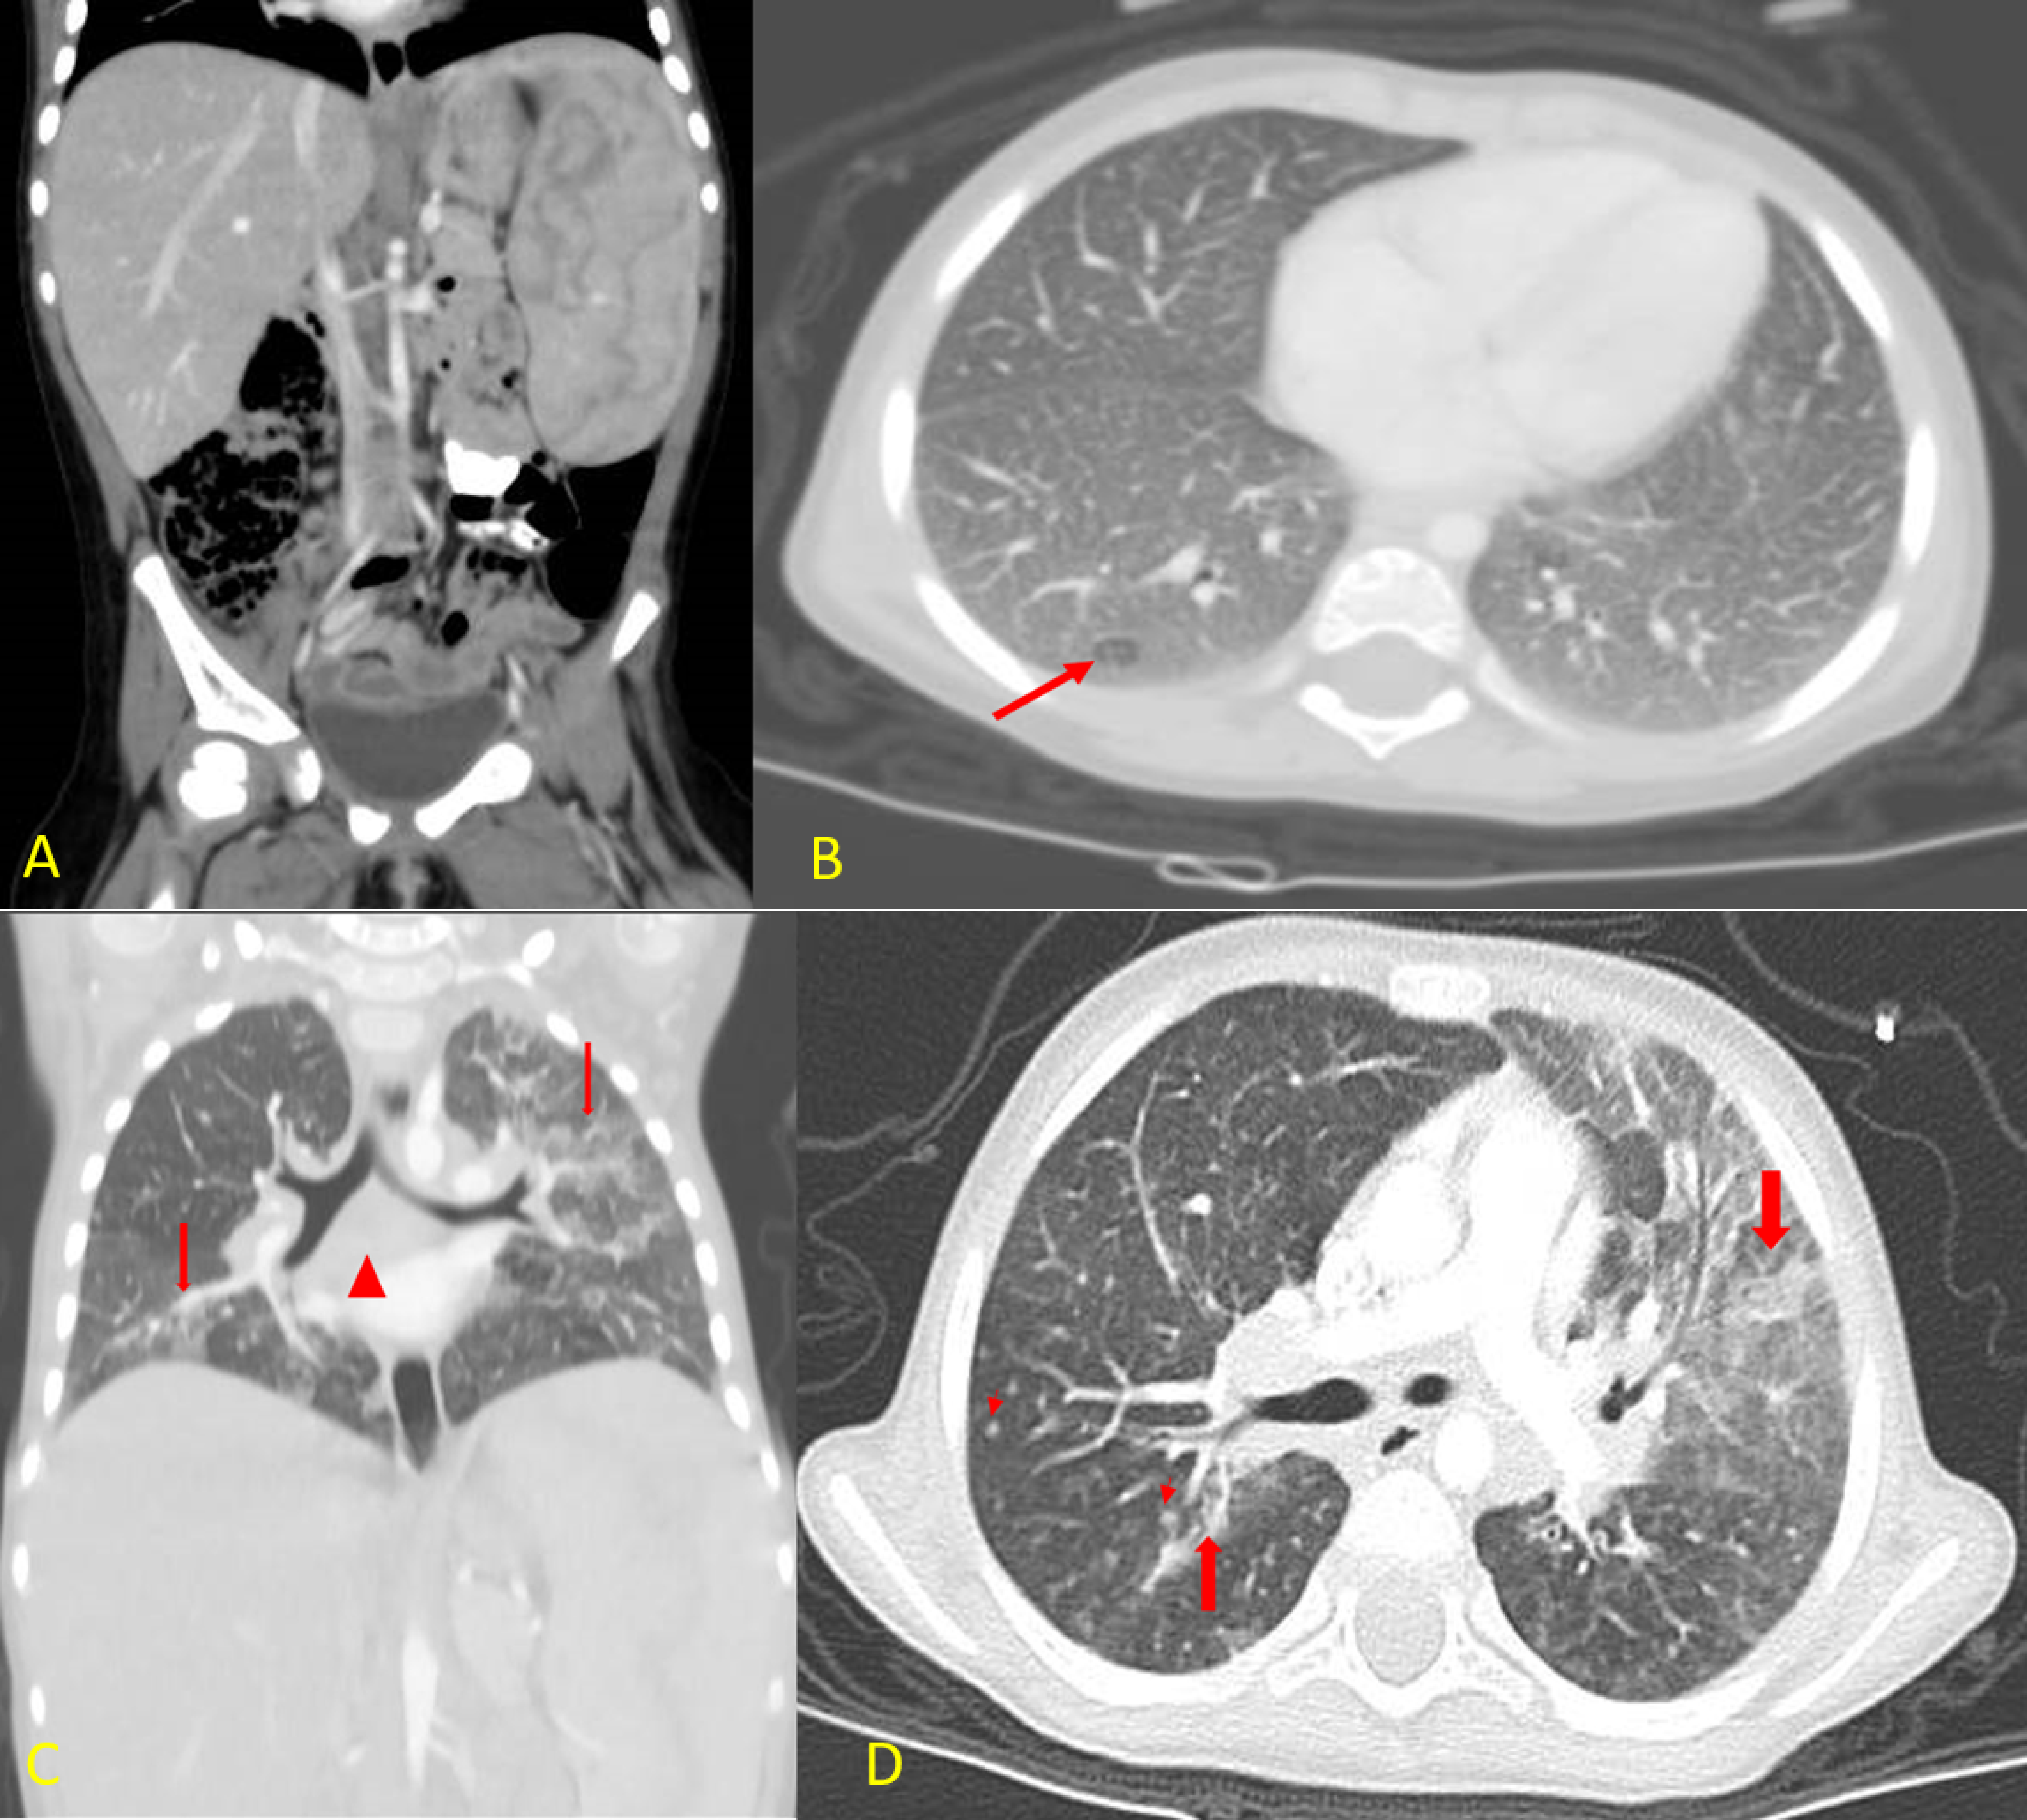

3.6. Recurrent Chest Infections and Chest CT Findings

3.7. Colonoscopy and Histopathological Findings